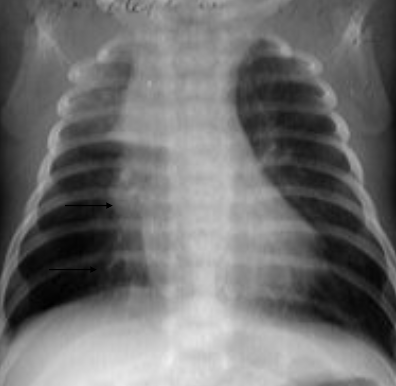

Rx toracică, incidență P-A

DESCRIERE:

DX: atelectazie prin NBP central endobronșic (pe bronhia principală stg)

DD: pleurezie masivă → caracter expansiv